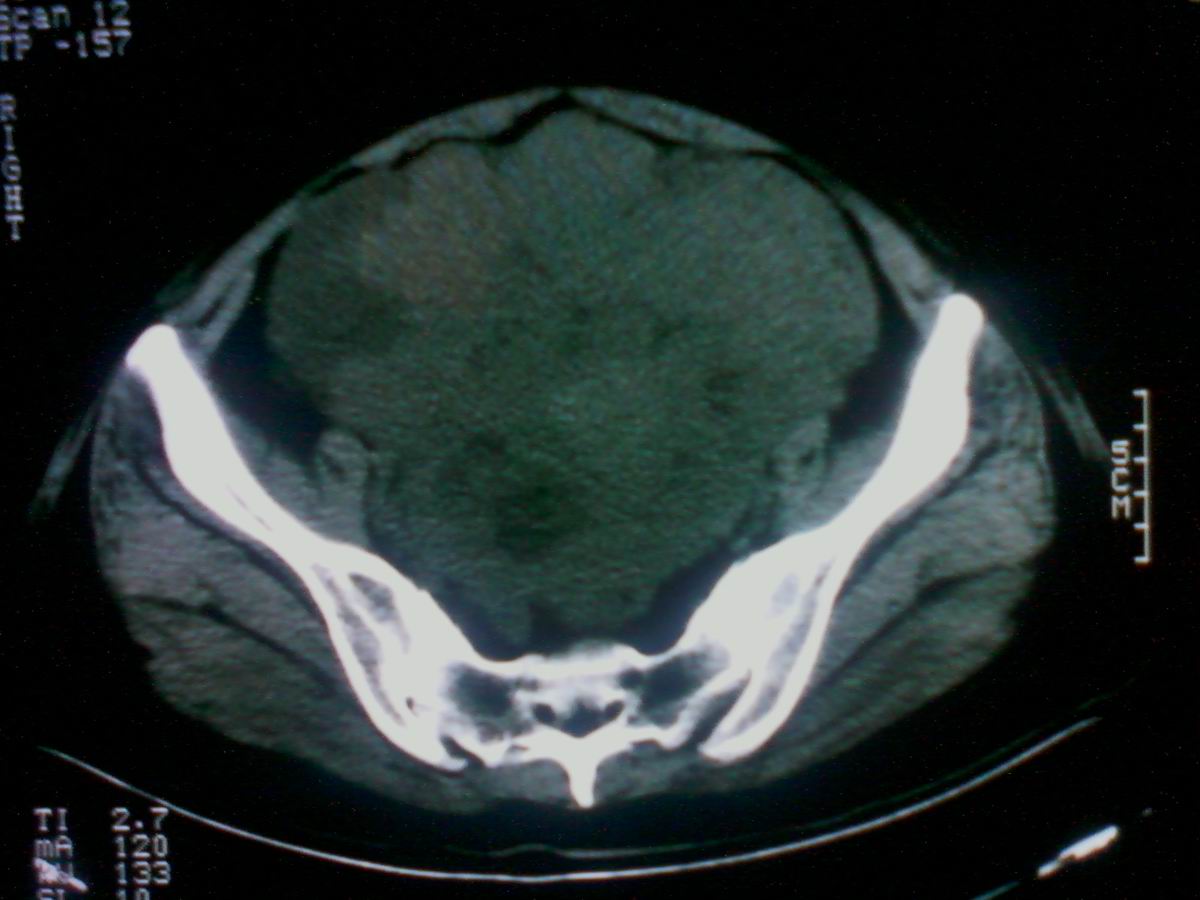

标题: CT25799:女性患者,45岁,腹胀,上腹部疼痛来诊,B超示盆腔 [打印本页]

标题: CT25799:女性患者,45岁,腹胀,上腹部疼痛来诊,B超示盆腔

考虑卵巢癌伴腹水

1)考虑卵巢恶性肿瘤。2)腹水。